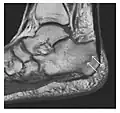

Fatigue fractures are more frequent in women which may be due to the relatively smaller bones of women. Moreover, pregnancy is a well-recognized risk factor for femoral neck fatigue fracture. While fibular and metatarsal fractures have a low risk of complications, other sites including the femoral neck, midanterior tibia, navicular, talar, and other intraarticular fractures are prone to complications such as delayed union, nonunion, and displacement. The site of the insufficiency fracture may be specific to the activity: for example, rugby and basketball players are more prone to navicular fractures, while gymnasts have a higher risk for talar fractures (Figure 7). Long distance runners are at increased risk for pelvic, tibial (Figures 8 and 9), and fibular fractures. In the military, calcaneus (Figure 10) and metatarsals are the most commonly cited injuries, especially in new recruits. Billiard players are at risk for upper limb fractures (Figure 11).[1]

Figure 7: Fatigue fracture of the talus in a 25-year-old male basketball player with right hind foot and ankle pain, without history of trauma, and a normal initial radiograph (not shown). (a) One-month followup lateral radiograph shows normal appearance. (b) Sagittal T1-weighted MRI shows an irregular fracture line (arrow) within an ill-defined area of hypointensity corresponding to bone marrow edema.[1]